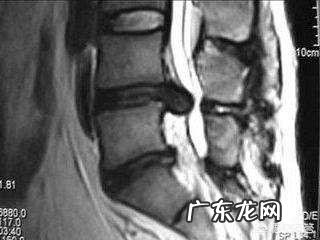

2、磁共振(MRI):对软组织的分辨率高,比之CT能更清晰显示椎间盘、腰椎韧带、有无椎管狭窄、椎管肿瘤等,但对于骨头的检查效果不如CT 。